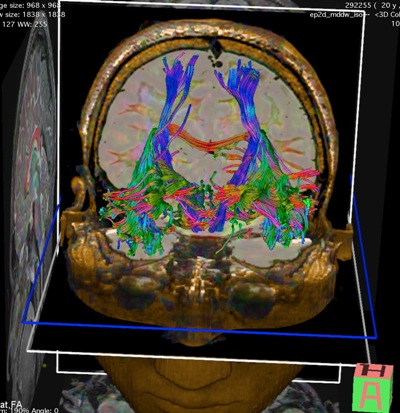

Cazul s-a dovedit a fi unul din categoria celor cu dificultate majoră. Pe lângă dimensiunile mari ale tumorii, a edemului cerebral perilezional, s-a constatat că tumoarea se află în vecinătatea imediată a zonelor verbale care ar putea suferi în timpul operației tradiționale. Pentru a elucida mai bine rapoartele anatomice, pacientul a realizat o investigație RMN cu utilizarea mai multor regimuri speciale: regim neuronavigație, DTI, DWI, Fiber Tracking și Mappingul Cortical preoperator prin Rezonanță Magnetică Funcțională – fMRI. Astfel, echipa chirurgicală a obținut informații foarte utile despre rapoartele anatomice regionale și distribuția diferitor funcții pe scoarța cerebrală. Aceste date au fost necesare pentru integrarea cu sistemul de neuronavigație.